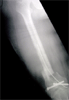

Healed but developed malunion and knee osteoarthritis, treated with intrarticular correction and knee replacement

Post

Op

2nd surgery : Good restoration alignment and pain relief